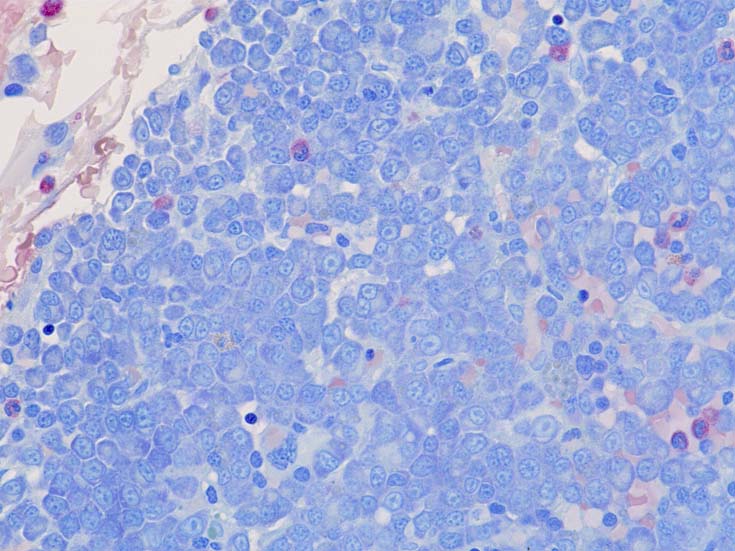

normal plasma cell, myeloma cell, plasmacytoma(bone)の細胞組織像

(サムネイル画像のクリックで大きな画像が見られます) 1-3はASD-Giemsa染色. 4はHE.

PC-MM-IHC.jpg